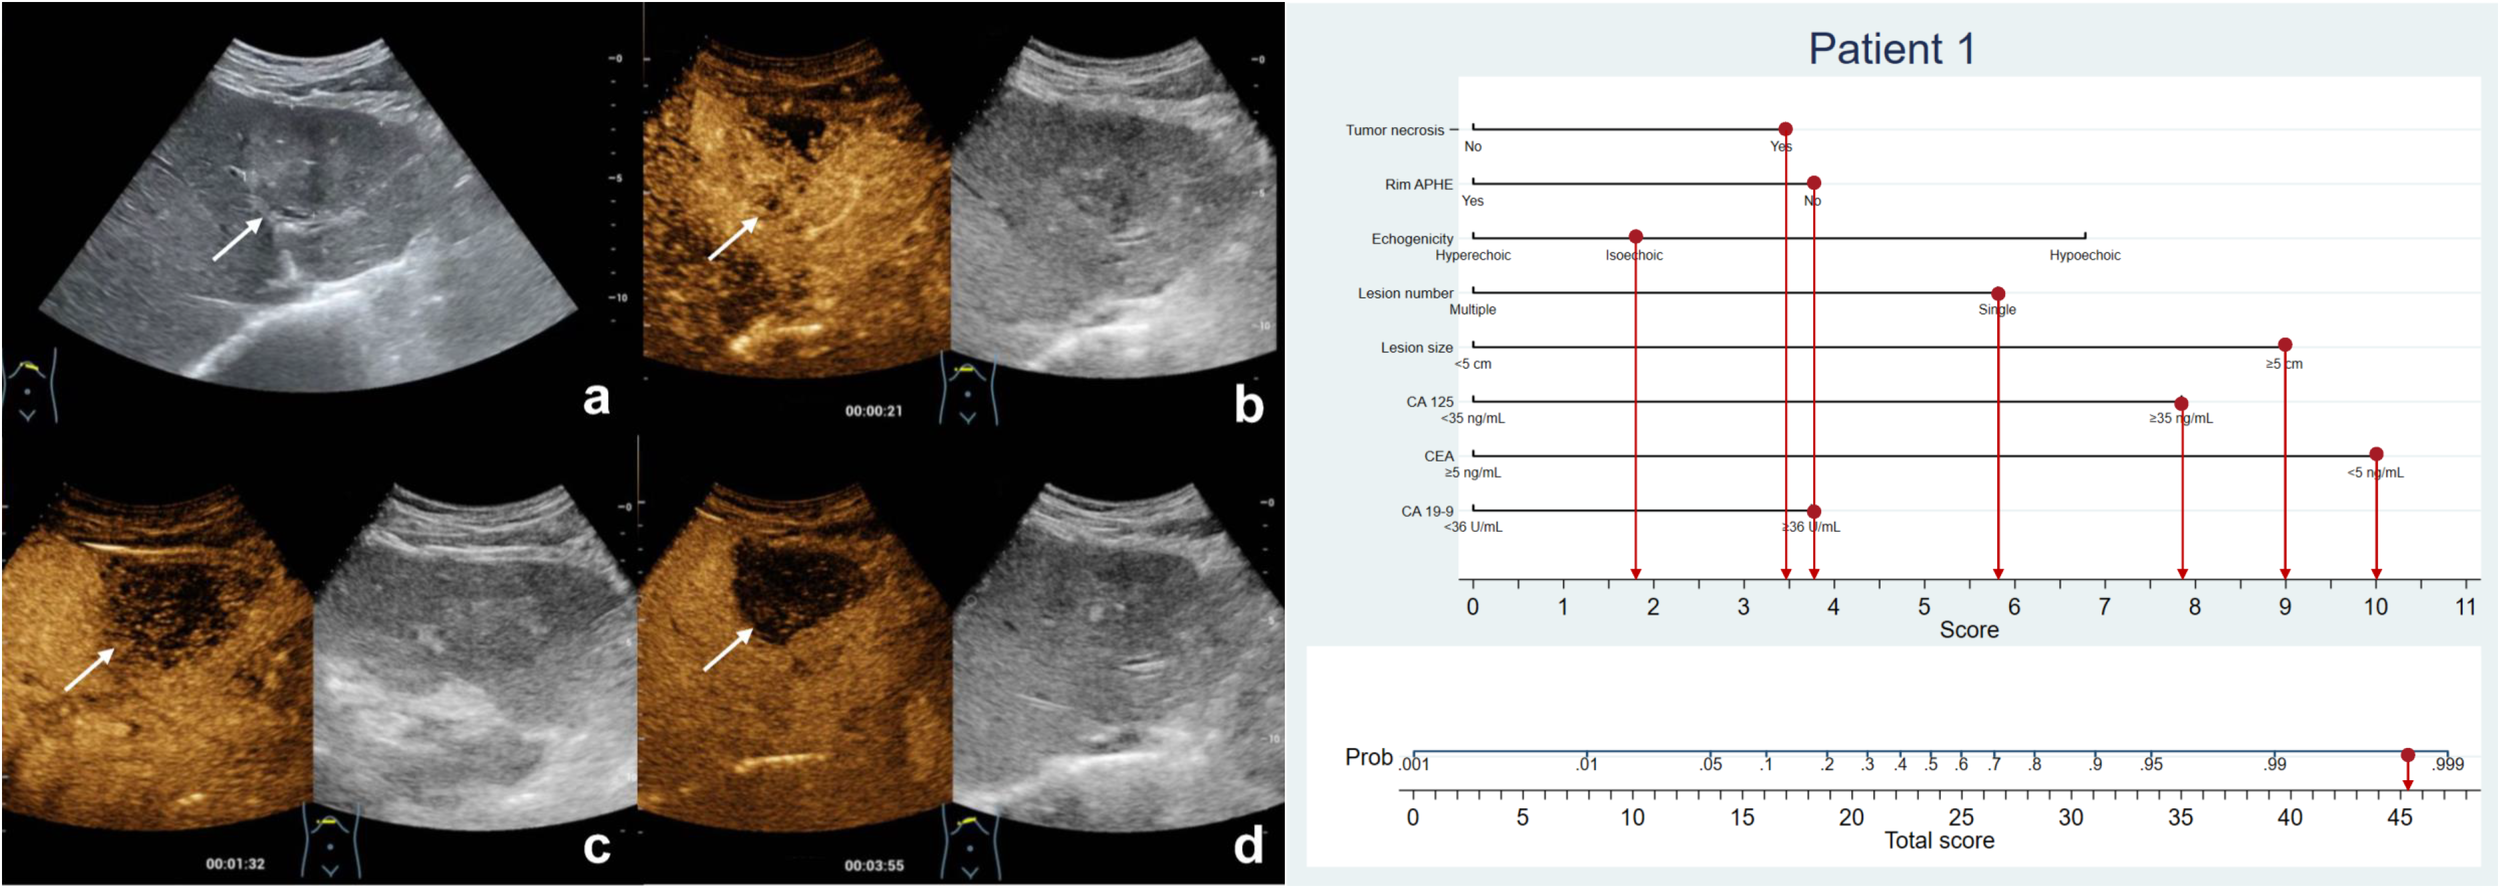

Figure 3 The patient was a 57-year-old man with a 6.1-cm isoechoic solid lesion in the liver (A). Hetero-hyperenhancement was observed during the arterial phase (B), and the lesion showed necrosis areas in the central on contrast-enhanced ultrasound (B–D). The serum level of CA125 and CA19-9 were elevated, while CEA level was normal. Based on the nomogram, a total of 45.2 points were assigned to the patient, corresponding to a probability of more than 90% of having MF-ICC. Postoperative pathological examination confirmed the diagnosis of MF-ICC.

Figure 4 The patient was a 75-year-old female who presented with several hypoechoic lesions in liver, with the largest one measuring 2.5-cm in diameter (A). Rim hyperenhancement of the tumor was observed during the arterial phase (B), and contrast-enhanced ultrasound revealed necrotic areas within the tumor (B–D). The patient exhibited elevated serum CEA levels but normal CA19-9 and CA125 levels. The nomogram score assigned to the patient was 10.2, indicating a less than 10% chance of developing MF-ICC. Pathological analysis confirmed liver metastatic adenocarcinoma originating from colon.